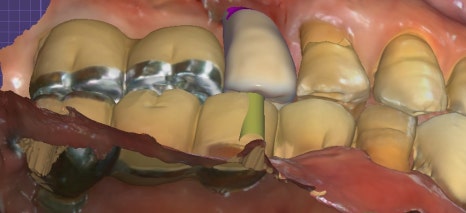

Second photo: Intraoral view after treatment.

The front tooth crowns and molar implant prosthetics were completed, resulting in a proper bite and greatly reduced discomfort while eating.

Third photo: A digital prosthetic design image captured with an intraoral scanner. All prosthetics were precisely fabricated in the hospital’s in-house dental laboratory.

The implants integrated stably, and two months later the prosthetic work for the upper right premolar implant was also completed.